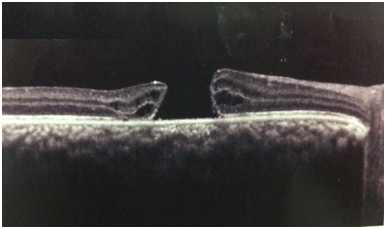

Optical coherence tomography (OCT) was performed to confirm the macular hole seen at the fundus examination (Figure 1). The patient was surgically treated with posterior pars plana vitrectomy and peeling of the internal limiting membrane with the aid of the Brilliant Blue dye, followed by tamponade with SF6 gas. It progressed satisfactorily after surgery, with improvement of visual acuity and absence of macular hole at funduscopy. At OCT, it presented macula compatible with post-surgical reorganization, with no evidence of a macular hole. About 1year after the procedure, the patient presented visual acuity of 20/80 with the best correction in OD and no evidence of macular hole to the OCT (Figure 2).

Figure 1 Preoperative OCT presenting with a macular hole.